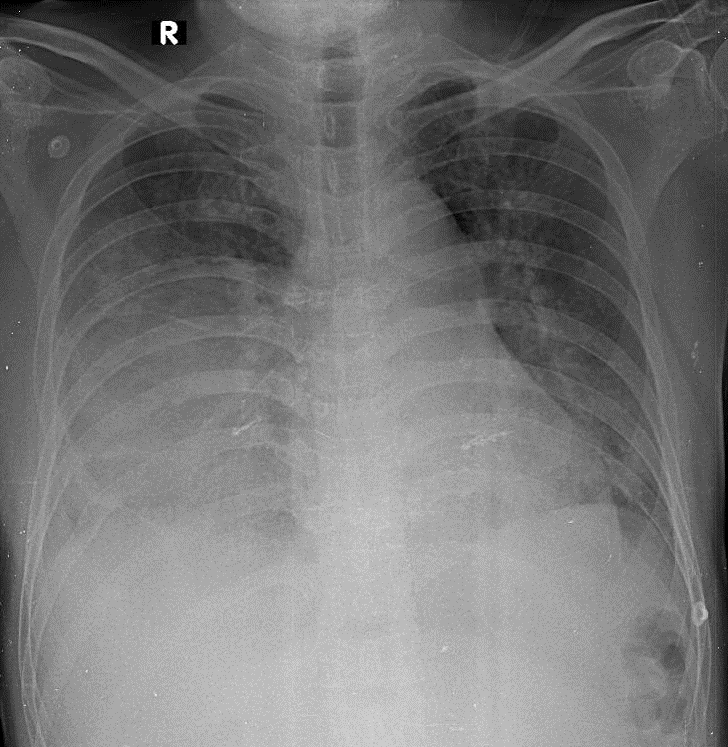

1-Thâm nhiễm phế nang lan tỏa hai phổi => Viêm phổi 2-Tràn dịch màng phổi (P)